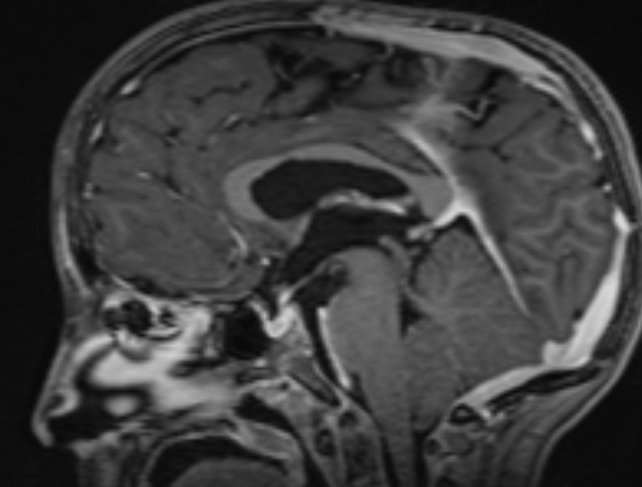

Please find below some images from the case:

OCT from early Jan 2026, when she first re-presented with vision loss in the left eye and disc edema. Very poor quality with poor fixation, but you can get a better sense of the left optic disc edema from the macular images.

Better quality OCT from the end of Jan after the shunt placement. The macular rasters don't catch the disc this time, so it's hard to compare, but I'd say the edema has clearly improved.

Post op MRI shows no significant change in the size of the ventricles, low lying cerebellar tonsils, similar to previous. Chiasm and nerves are small, unchanged from an MRI one year ago.

Here is an image of the spine from a year ago, showing syringomyelia, which has been unchanged for several years.